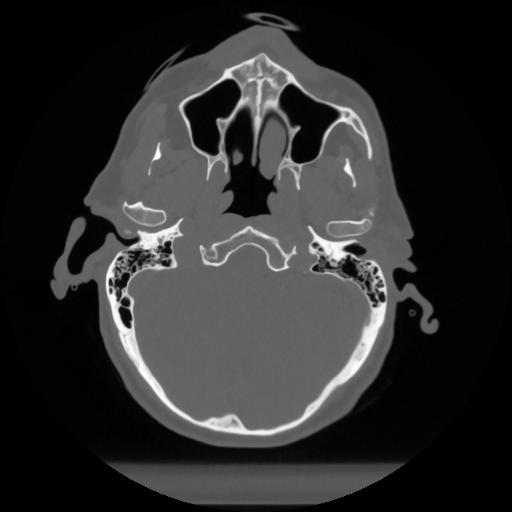

12 P.BLANDAS,,Vol,0.5,P.BLANDAS,,